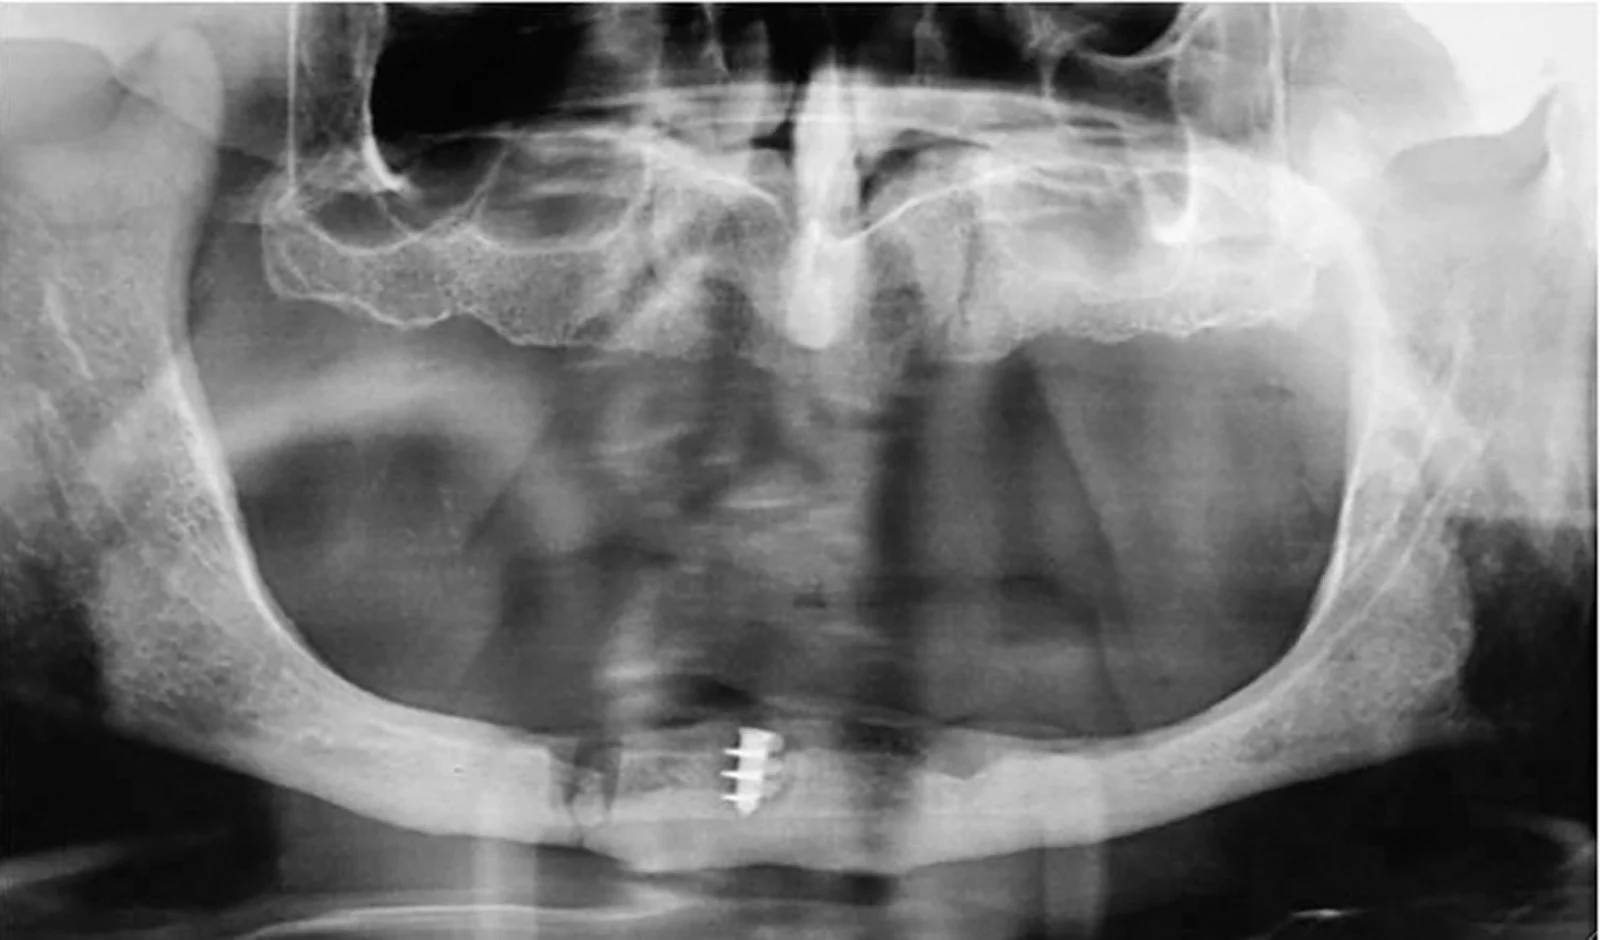

Il primo passo fondamentale è una valutazione clinica approfondita. Durante questa fase, il dentista raccoglie informazioni importanti attraverso:- Anamnesi medica e odontoiatrica dettagliata

- Esame obiettivo del cavo orale e dei tessuti periorali

- Radiografie endorali, panoramiche o TAC 3D

- Impronte delle arcate dentarie per lo studio dei modelli

- Analisi occlusale e gnatologica per valutare i rapporti tra le arcate